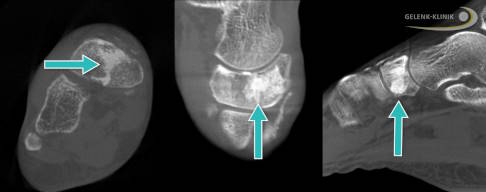

Beim Verdacht auf einen navikulären Ermüdungsbruch wird die Bildgebung eingeleitet. Meist führt man zunächst eine belastete Röntgenaufnahme einschließlich Schrägaufnahme durch. Allerdings sind Röntgenbilder oft erst einmal negativ. Hilfreicher ist die digitale Volumentomographie (DVT). Mit ihr lassen sich Frakturlinien besser erkennen und auch Fissuren, also winzige Risse im Knochen, gut darstellen. Eine kernspintomographische Untersuchung (MRT) ist ebenfalls möglich, bei deutlichem klinischem Verdacht aber nicht unbedingt erforderlich. Die MRT kann jedoch helfen, wichtige Differenzialdiagnosen auszuschließen.

Eine besonders wichtige Differenzialdiagnose ist das zweigeteilte Kahnbein (Os naviculare bipartitum). Es lässt sich in der Regel sowohl in Röntgen- als auch auch in CT- und MRT-Aufnahmen gut erkennen. Für das zweigeteilte Kahnbein spricht, wenn das verdächtige Knochenteil oder -fragment abgerundet ist. Auch die Unterscheidung zwischen einer akuten Fraktur und einem Ermüdungsbruch ist in der Bildgebung möglich. So zeigt z. B. die Stressfraktur im Gegensatz zum akuten Bruch oft eine stärkere Sklerosierung. Eine weitere Differenzialdiagnose ist die Osteonekrose des Kahnbeins, das Müller-Weiss-Syndrom.

Digitale Volumentomographie (DVT) zur Diagnostik und OP-Planung

Zur Stellung der exakten Diagnose einer Stressfraktur werden häufig mehrere bildgebende Verfahren wie die digitale Volumentomographie (DVT), die Computertomographie (CT) oder die Magnetresonanztomographie (MRT) miteinander kombiniert.

Die vielversprechendste Möglichkeit zur Erkennung von Stressfrakturen im Bereich der Fußgelenke ist die digitale Volumentomographie (DVT). Dieses radiologische Verfahren macht Knochen- und Gelenkveränderungen durch die Erstellung von Schnittbildern bereits im Anfangsstadium der Erkrankung sichtbar. Häufig entstehen Stressfrakturen am Fuß im Bereich des Innenknöchels mit Beteiligung des Sprunggelenks, wo sie durch die DVT schon früh nach dem Auftreten erster Symptome erkannt werden können. Im Gegensatz zum MRT-Bild sind für die Diagnosestellung mittels DVT allerdings immer Veränderungen der Knochenstruktur notwendig, um Stressfrakturen sicher zu ermitteln. Das bildgebende Verfahren wird neben der Diagnostik auch zur Operationsplanung eingesetzt.